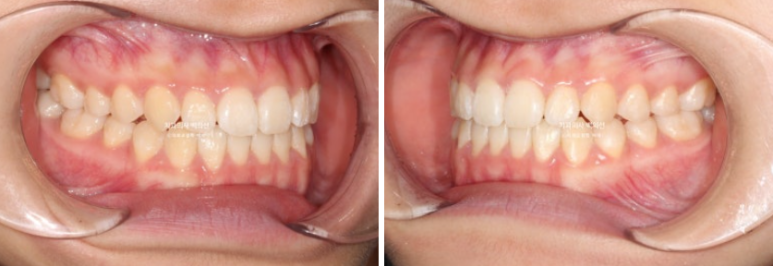

23.10

앞니에 개방교합이 보이고 앞니뿐 아니라 어금니까지 반대교합이 보입니다.

사진처럼 양쪽 어금니가 모두 거꾸로 물릴 정도로 위턱이 좁다면 악궁확장장치를 먼저 따로 써야 합니다.

치아를 품는 뼈의 면적을 늘려주어야 잇몸에 무리없이 좋은 결과가 나옵니다.